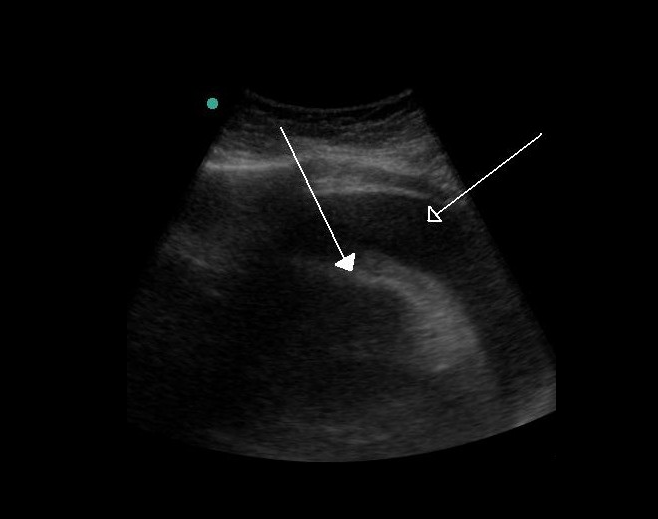

- 정기적인 심전도(EKG) 및 심장 초음파 검사(Echocardiogram)를 통해 심장 상태를 모니터링하고, 심장 기능이 악화되지 않도록 관리해야 합니다.